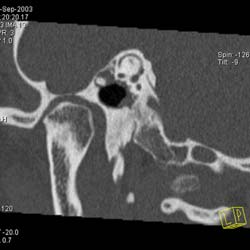

Рис. 10. Принципы КТ высокого разрешения (КТВР) на примере исследования

пирамиды височной кости. Применены тонкие срезы (0.5 мм) и "острый" алгоритм

реконструкции (кернель 90). (Слева) отчетливо видны элементы внутреннего

уха - улитка, полукружные канальцы. (В центре) показана проекция продольного

сечения височно-нижнечелюстного сустава. (Справа) - холестеатома.